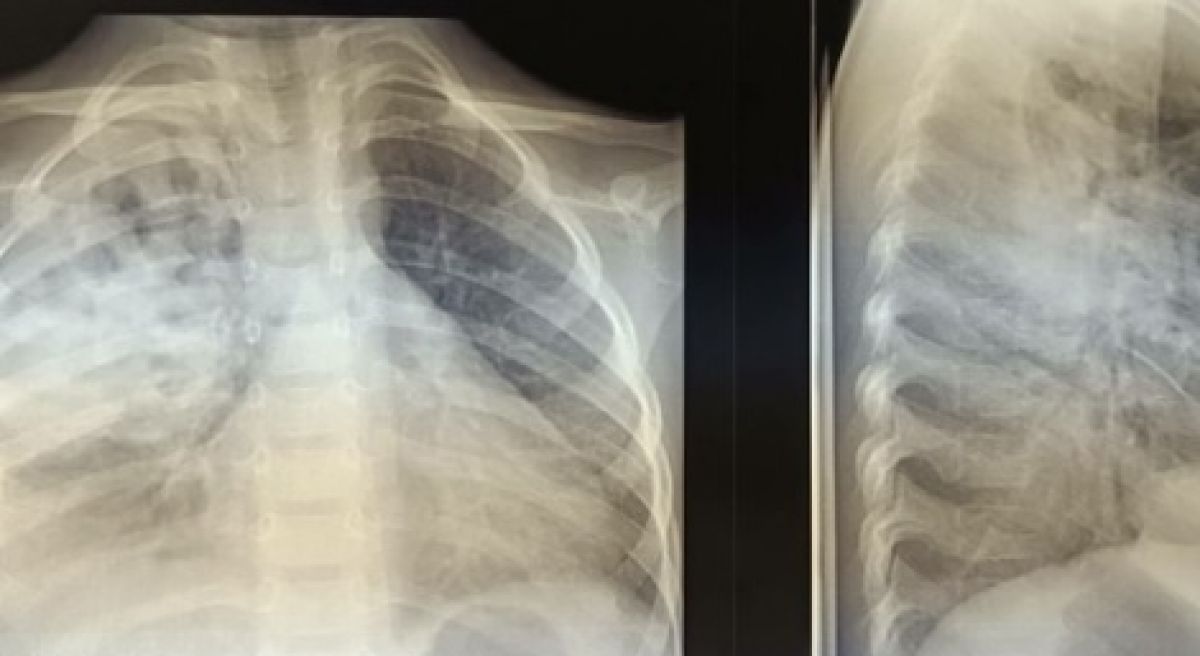

Владимирские врачи вылечили ребенка от тяжелой формы гнойной пневмонии Врачи-педиатры смогли поставить на ноги ребенка с тяжелой формы пневмонии со скоплением гноя и воздуха в плевральной полости,

Врачи-педиатры смогли поставить на ноги ребенка с тяжелой формы пневмонии со скоплением гноя и воздуха в плевральной полости, рассказали в областной детской клинической больнице.

По словам медиков, потребовалось проведение  дренирования плевральной полости. Затем юному пациенту назначили физиотерапию и подобрали терапию. В настоящее время малыш уже выписан домой.

Врачи также добавили, в раннем возрасте смертность от данного заболевания относительно высока.